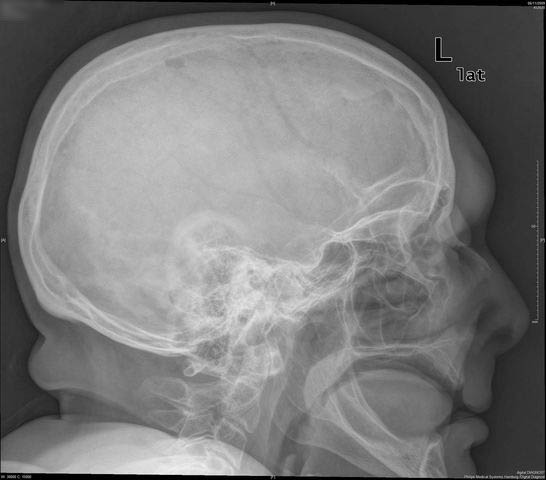

Higroma frontal bilateral

TC exostosis occipital congénica.

TC exostosis occipital congénita.